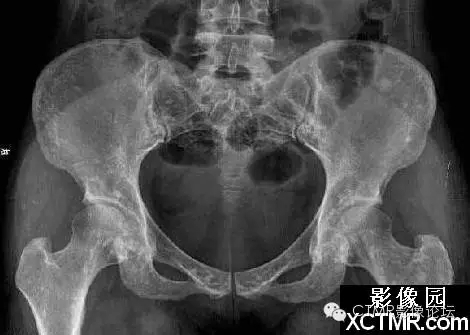

骨斑點癥是一種罕見病,可無任何臨床癥狀。是由于骨內(nèi)具有彌漫性斑點狀致密骨質(zhì)而得名。既往文獻曾稱局限性骨質(zhì)增生癥、彌漫性濃縮性骨病、家族性彌漫性骨硬化癥、點狀致密骨病等。特點為松質(zhì)骨內(nèi)有彌漫性圓點狀致密影。臨床上可無任何癥狀,一般為X線檢查所發(fā)現(xiàn)。可見于任何年齡,男多于女。血鈣、磷正常。

骨斑點癥具有以下特點:

(1)本病無臨床癥狀,均為查體或檢查其它病時發(fā)現(xiàn)本病。

(2)本病與年齡性別無關(guān),本組從22~58歲,文獻報道年齡從4個月~90歲均有發(fā)病。

(3)病灶呈彌漫性多發(fā)的密度增大的圓形、橢圓形、圓圈狀、結(jié)節(jié)狀陰影,其形態(tài)走行,部分與骨的長軸一致。

(4)病灶多累及長骨的兩端,密集于干骺端及骨骺,以及骨盆、手、足及不規(guī)則骨。越靠近關(guān)節(jié)病灶越密集,且密度越濃。病灶可相互融合成片而遮蓋正常骨組織。

(5)密度增濃的斑點狀病灶的邊緣不甚清晰銳利,越靠近中心部位密度越濃,邊緣部位密度略淡。

(6)病灶侵及骨的松質(zhì)骨。骨膜及關(guān)節(jié)軟骨不受侵犯,故關(guān)節(jié)間隙光整清晰。

(7)ECT檢查見顯影后骨骼放射性分布不均勻,骨松質(zhì)內(nèi)有多個大小不等的骨鈣化灶。骨顯像對應(yīng)性放射性增強。據(jù)上述表現(xiàn)視全身骨顯像多處骨代謝增強灶,為骨質(zhì)代謝異常。

(8)本病應(yīng)與成骨性轉(zhuǎn)移相鑒別。成骨性轉(zhuǎn)移首先應(yīng)有原發(fā)性病灶并轉(zhuǎn)移灶呈單發(fā)或散在多發(fā)性骨質(zhì)增濃病灶,無密集對稱性。其病灶直徑均較大,直徑一般在1.0cm以上,同時伴有明顯的疼痛癥狀。與本病鑒別不難。還應(yīng)與蠟淚樣骨相鑒別。